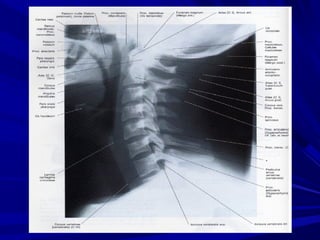

 En önemli ve vazgeçilmez tetkik lateral servikal grafidir.

– C7’ yi de gösteren tam lateral radyografi ile % 70 – 85

oranında tanıya varılabilir.

– Görüntüleme zorluğundan C7 – T1’ i içeren servikotarasik

bileşke yaralanmaları görülmeyebilip atlanabilir.

– Servikal omurganın radyolojik muayenesinde;

– Lateral, ön – arka (AP) ve ağız açık AP(odontoid)

grafilerden oluşur.